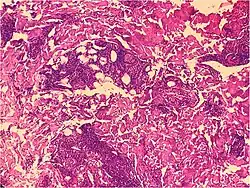

Psoriaform dermatitis

Examining multiple deeper levels is recommended if initial cuts do not correlate well with the clinical history.[2]

Psoriaform dermatitis typically displays:[2]

- Regular epidermal hyperplasia, elongation of the rete ridges, hyperkeratosis, and parakeratosis.

- Usually:A superficial perivascular inflammatory infiltrate

- Often: Thinning of epidermal cells overlying the tips of dermal papillae (suprapapillary plates), and dilated, tortuous blood vessels within these papillae